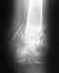

íÏÑ ÐÏÄÒÕÇÁ ÎÁ ÇÅÍÏÄÉÁÌÉÚÅ Ó 2001Ç.ä×Å ÎÅÄÅÌÉ ÎÁÚÁÄ ÎÁÞÁÌÉÓØ ÓÉÌØÎÙÅ ÂÏÌÉ ÍÅÖÄÕ ÌÏÐÁÔÏË É ÏÔËÁÚÁÌÉ ÎÏÇÉ.ðÏÓÌÅ ÏÓÍÏÔÒÁ É ÔÏÍÏÇÒÁÆÁ ÂÙÌ ÐÏÓÔÁ×ÌÅÎ ÄÉÁÇÎÏÚ:ÐÁÔÏÌÏÇÉÞÅÓËÉÊ ËÏÍÐÒÅÓÓÉÏÎÎÙÊ ÐÅÒÅÌÏÍ ÔÅÌÁ Th1 ÐÏÚ×ÏÎËÁ ÏÓÌÏÖÎÅÎÎÙÊ ÎÉÖÎÉÍ ÐÁÒÅÚÏÍ.÷ÓÅ ÅÝÅ ÏÓÌÏÖÎÅÎÏ ×ÔÏÒÉÞÎÙÍ ÇÉÐÅÒÐÁÒÁÔÅÒÉÏÚÏÍ,×ÔÏÒÉÞÎÏÊ ÁÎÅÍÉÅÊ,ÇÅÐÁÔÉÔ ÷,C.÷ÏÚÍÏÖÎÁ ÌÉ ÏÐÅÒÁÃÉÑ ÐÏ ×ÏÓÓÔÁÎÏ×ÌÅÎÉÀ ÐÏÚ×ÏÎÏÞÎÉË × ÅÅ ÓÌÕÞÁÅ?åÓÌÉ ×ÏÚÍÏÖÎÁ,ÔÏ ËÕÄÁ ÌÕÞÛÅ ÏÂÒÁÔÉÔÓÑ?